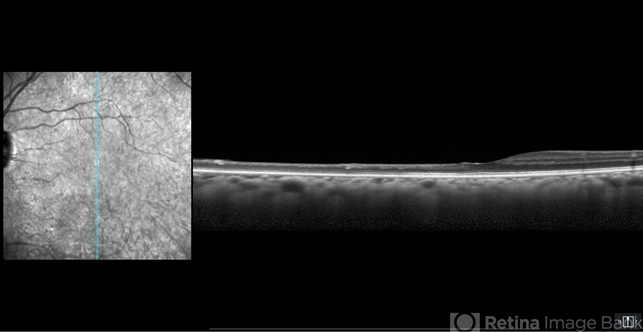

- OCT image of a 54-year-old female with an asymptomatic chronic branch retinal artery occlusion in the left eye showing inner retinal atrophy in the inferior macula corresponding to the region of chronic ischemia. Vision was 20/20.